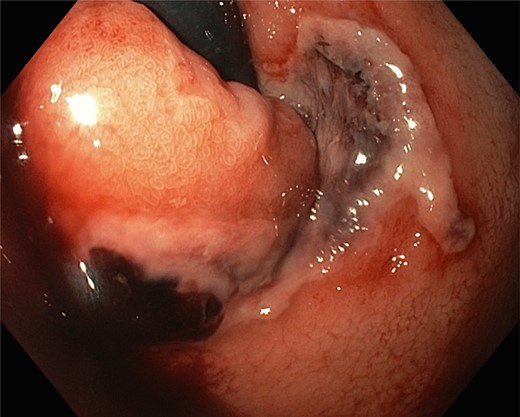

Gastroscopy the following day showed a fundal gastric ulcer and the MWT, which was now larger and deeper (Fig. 2). On Day 10, the patient underwent surgery. A midline laparotomy incision was performed, followed by extensive adhesiolysis. After the anterior wall of the stomach was exposed from the GEJ to pylorus, a longitudinal gastrotomy was created over the fundus. There was a deep MWT at GEJ extending along the greater curve of the stomach, which was bleeding actively. The MWT was oversewn with interrupted 3/0 PDS sutures and hemostasis achieved. A second, larger fundal ulcer, presumably from pressure necrosis of SB tube, was also noted. This ulcer occupied most of the fundus of stomach, which was excluded from the gastric cavity, by the closure of fundus with interrupted 3/0 PDS (Fig. 3). Postoperatively, oral fluids were commenced on Day 12. On Day 15, a Gastrografin swallow study was normal, and oral intake was encouraged. The patient recovered without complications and returned to the rehabilitation facility.

The gastric ulcer was excluded from the rest of the stomach through gastrostomy using 3/0 PDS suture.